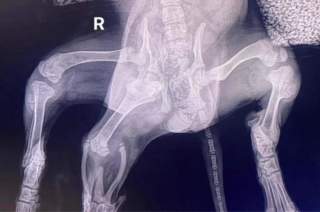

Là, la vétérinaire Charlotte Biddle a pris le relais en effectuant une série de radiographies afin de mieux comprendre les malformations d'Ariel, notamment deux pattes arrière supplémentaires et le début d'une seconde vulve. Il a également été constaté que son bassin ne s'était pas formé correctement à cause d'une articulation supplémentaire au niveau de la hanche.